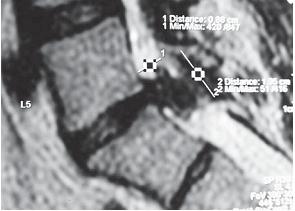

МРТ № 28

На МРТ № 28 наблюдается секвестрированная грыжа межпозвонкового диска в поясничном отделе позвоночника в сегменте LV—S1 с каудальной миграцией секвестра